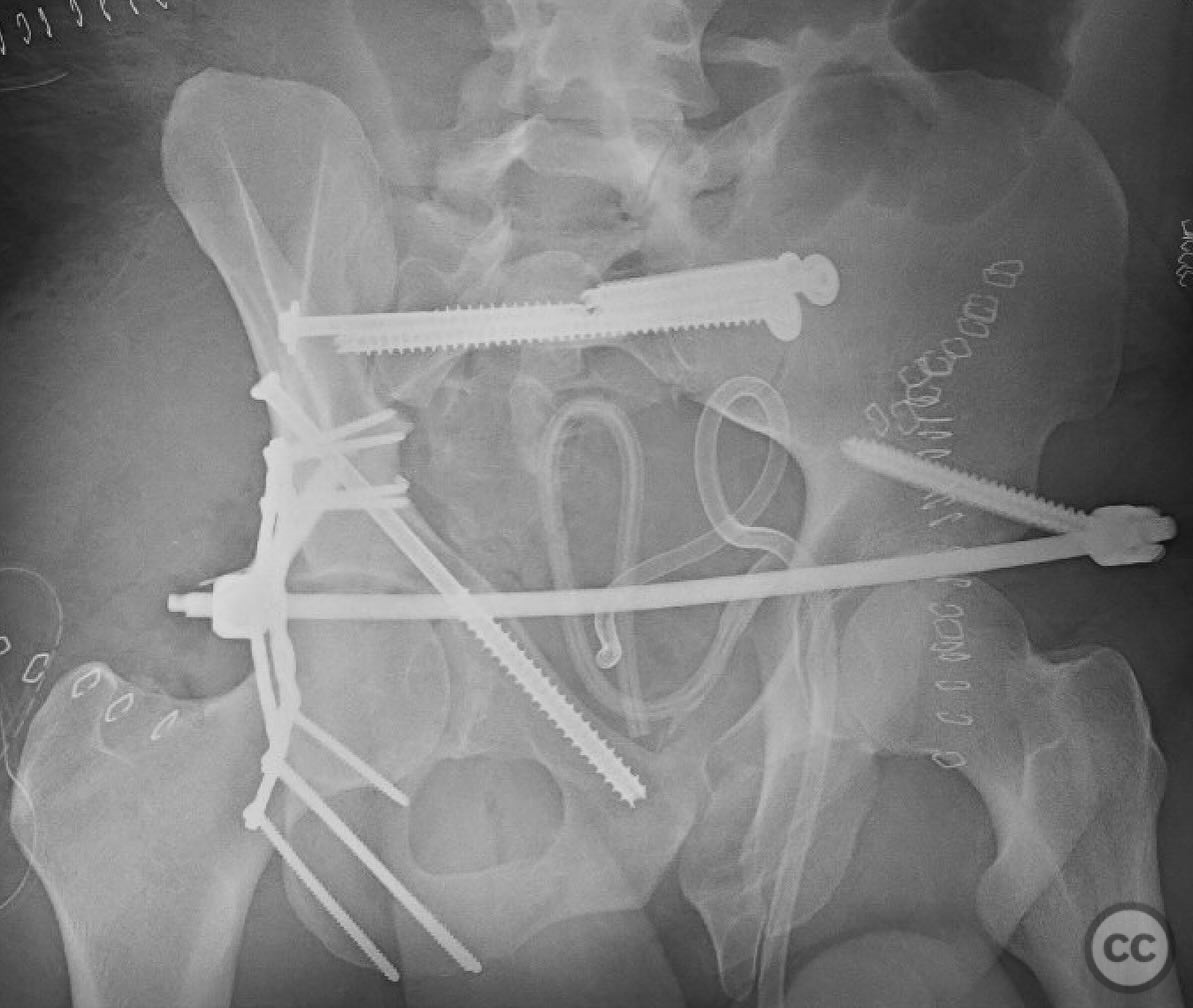

Combined Pelvic Ring and Transverse Acetabulum Fracture with Bladder Injury

Clinical and radiological findings:  The patient presented with a highly unstable pelvic ring injury and a transverse acetabulum fracture, accompanied by a bladder injury. The bladder injury was addressed emergently with a low vertical midline Pfannenstiel incision for repair, followed by the placement of a low right-sided suprapubic catheter. Radiological imaging confirmed the transverse acetabular fracture and disruption of the left sacroiliac joint, along with a displaced sacral fracture.

Planning remarks:  The preoperative plan involved a staged approach to address the combined injuries. Initially, the focus was on stabilizing the pelvic ring to provide a stable base for subsequent acetabular reconstruction. The left sacroiliac joint disruption was to be reduced and stabilized first, followed by lag screw fixation of the displaced sacral fracture. Additional screws were planned as anatomical corridors allowed. An external fixator was considered to support the posterior ring stabilization. The second stage involved open reduction and internal fixation (ORIF) of the acetabulum through a Kocher-Langenbeck approach, with potential anterior column fixation via the modified Stoppa approach if necessary.

Orthopaedic implants used:   Lag screws for sacroiliac joint and sacral fracture fixation, external fixator for posterior ring stabilization, potential plate and screw constructs for acetabular ORIF through Kocher-Langenbeck and modified Stoppa approaches.